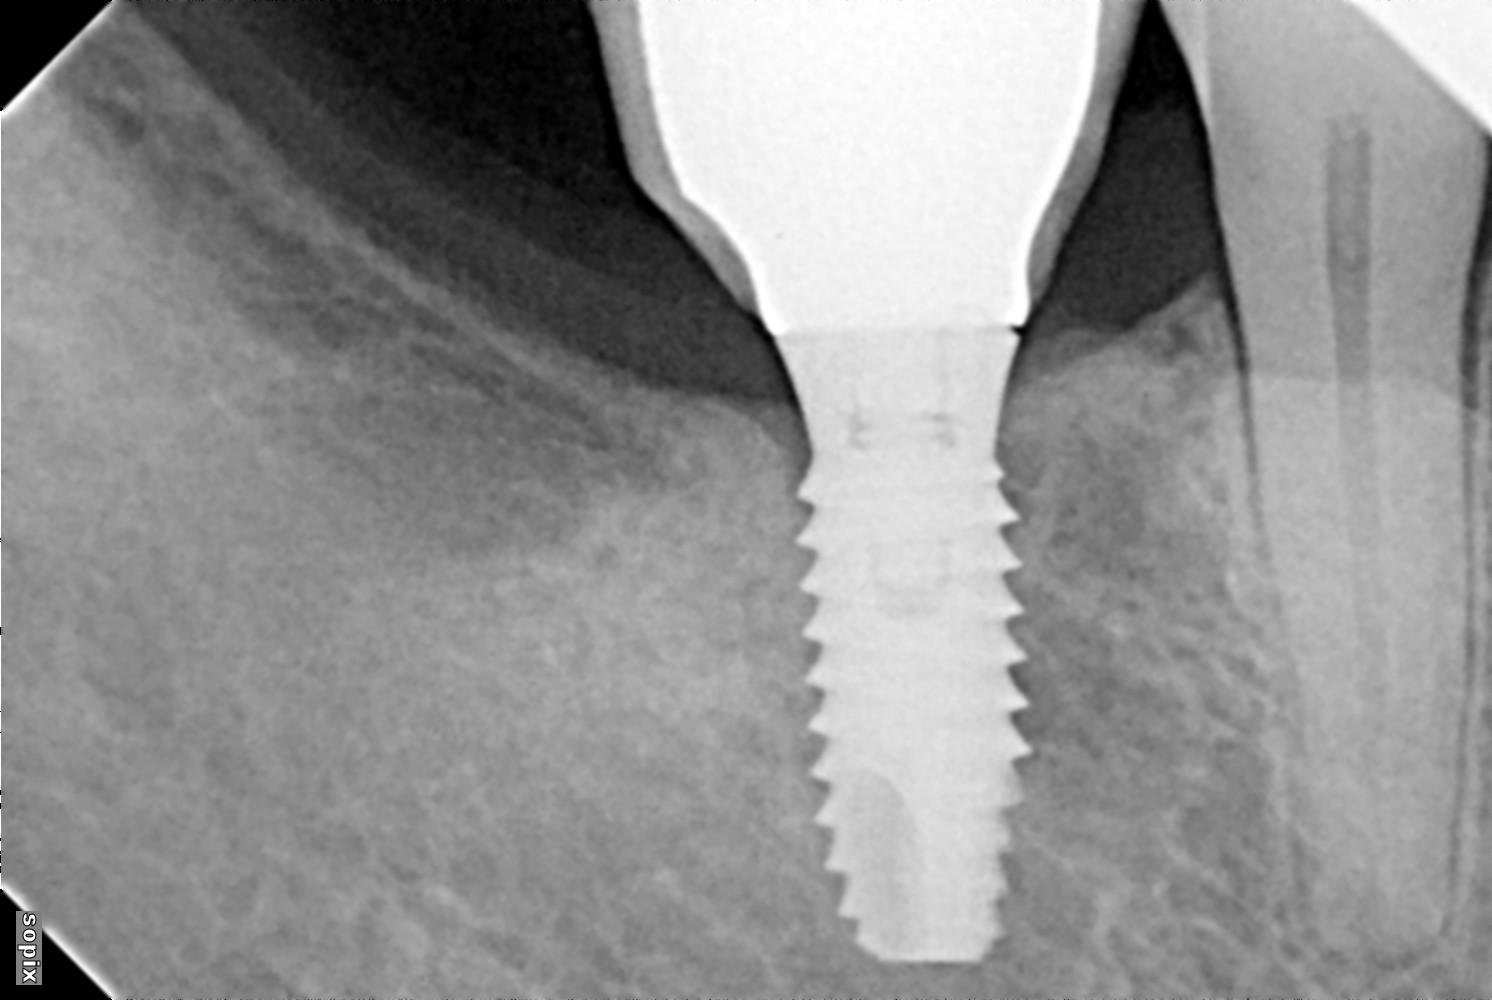

Necesitaría ayuda para identificar unos implantes que se les está aflojando la corona, el que está en posición del 36 fue colocado en Idental Málaga y rehabilitado en Dentix Vélez Málaga y el de la posición 46 fue colocado y rehabilitado por Déntix Vélez Málaga.

El implante que está situado en la pieza 36, se trata de un implante de conexión externa plataforma RP compatibles con Branemark 2.7 / 07. Es un implante ziacom modelo oex métrica de tornillo 2.0 mm. No vas a tener ningún problema para encontrar los aditamentos protésicos para rehabilitar ese implante.

El de la pieza 46, se trata de un implante phibo TSA modelo S3 o no sé si podría ser también modelo S4.

El destornillador es hexagonal 1.25 mm.